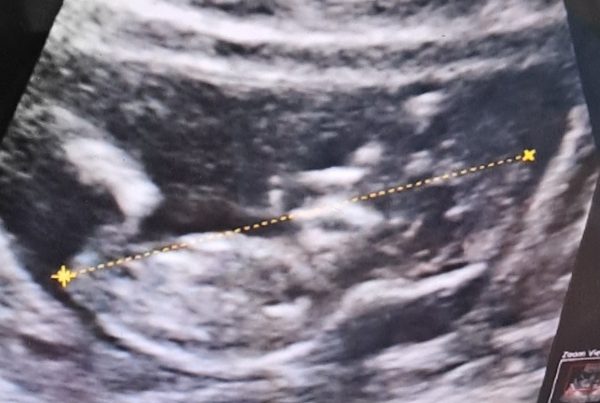

On Sunday, we triaged patients and made treatment plans and scheduled procedures. One of the patients scheduled for Dr Robinson today was a 16 year old girl. We had a plan for her. We knew the risks and explained them to her and her family. We started the procedure. We learned that her condition was worse than expected. We paused. Dr Robinson broke scrub and went to speak to her parents. Decisions were made and plans changed. An adjustment to the procedure left us all with heavy hearts.

Later, we rounded on our patients including the 16 year old. Her parents both stood by her side while Dr Robinson delivered the news to her that we had to amputate her finger due to an aggressive tumor. And while we all knew that it was the absolute right choice, it was hard to witness.